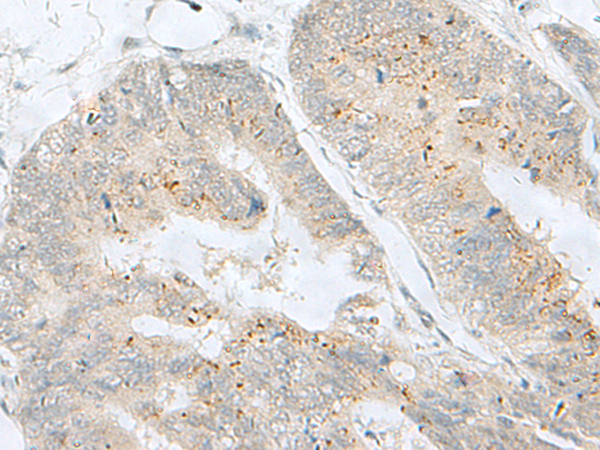

分类: 科研抗体货号: P11006别名: ADCAD2应用: IHC反应种属: Human, Mouse